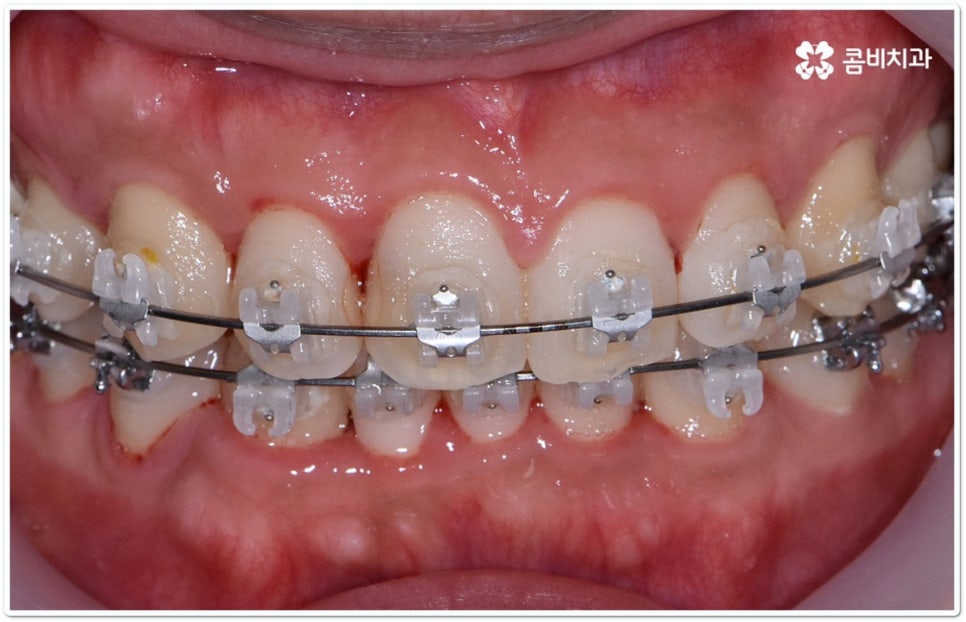

클리피씨교정 장치란 clippy-c 라는 단어 뜻에서 알 수 있듯이 클립이 달린 (clippy) 세라믹(ceramic) 브라켓 장치를 의미하고 있어요. 예전에 교정 장치에서 많이 쓰이던 방식은 고무줄 또는 미세철사를 이용하여 브라켓마다 각각 와이어를 묶어주는 것으로 날카롭게 잘린 철사 끝부분에 자칫 상처를 입을 수도 있고 한 달에 한 번 정도 치과에 내원하여 진행 상황에 따라 교정력을 조정하는 시간도 훨씬 더 많이 걸렸다고 할 수 있습니다.

이와는 다르게 클리피씨교정 장치는 자가결찰방식이라고 해서 각 브라켓에 여닫을 수 있는 특수한 클립(뚜껑)이 달려 있어 전체 와이어를 통과시켜 잡아주는 방식을 이용하기 때문에 겉면이 매끄럽고 진료 시간도 짧아지며 마찰로 빠져나가는 교정력을 줄여주어 좀 더 효율적으로 치아를 이동시킨다고 할 수 있어요. 즉 보다 적은 힘으로 지속적이고 부드러운 치아 이동을 가능하게 하므로 언급했던 것처럼 개인차가 있지만 전체 기간을 약 6개월 정도 단축시키고 치아가 이동할 때 느낄 수 있는 초기 통증도 감소시켜 줄 수 있는 거예요. 또한 치아 색상과 비슷한 세라믹 재질을 이용하기 때문에 음식을 먹거나 대화를 하는 등 입을 벌렸을 때 보일 수 있는 교정 장치가 그렇게 크게 눈에 띄지 않아 심미적으로도 뛰어나다는 장점을 가지고 있습니다.